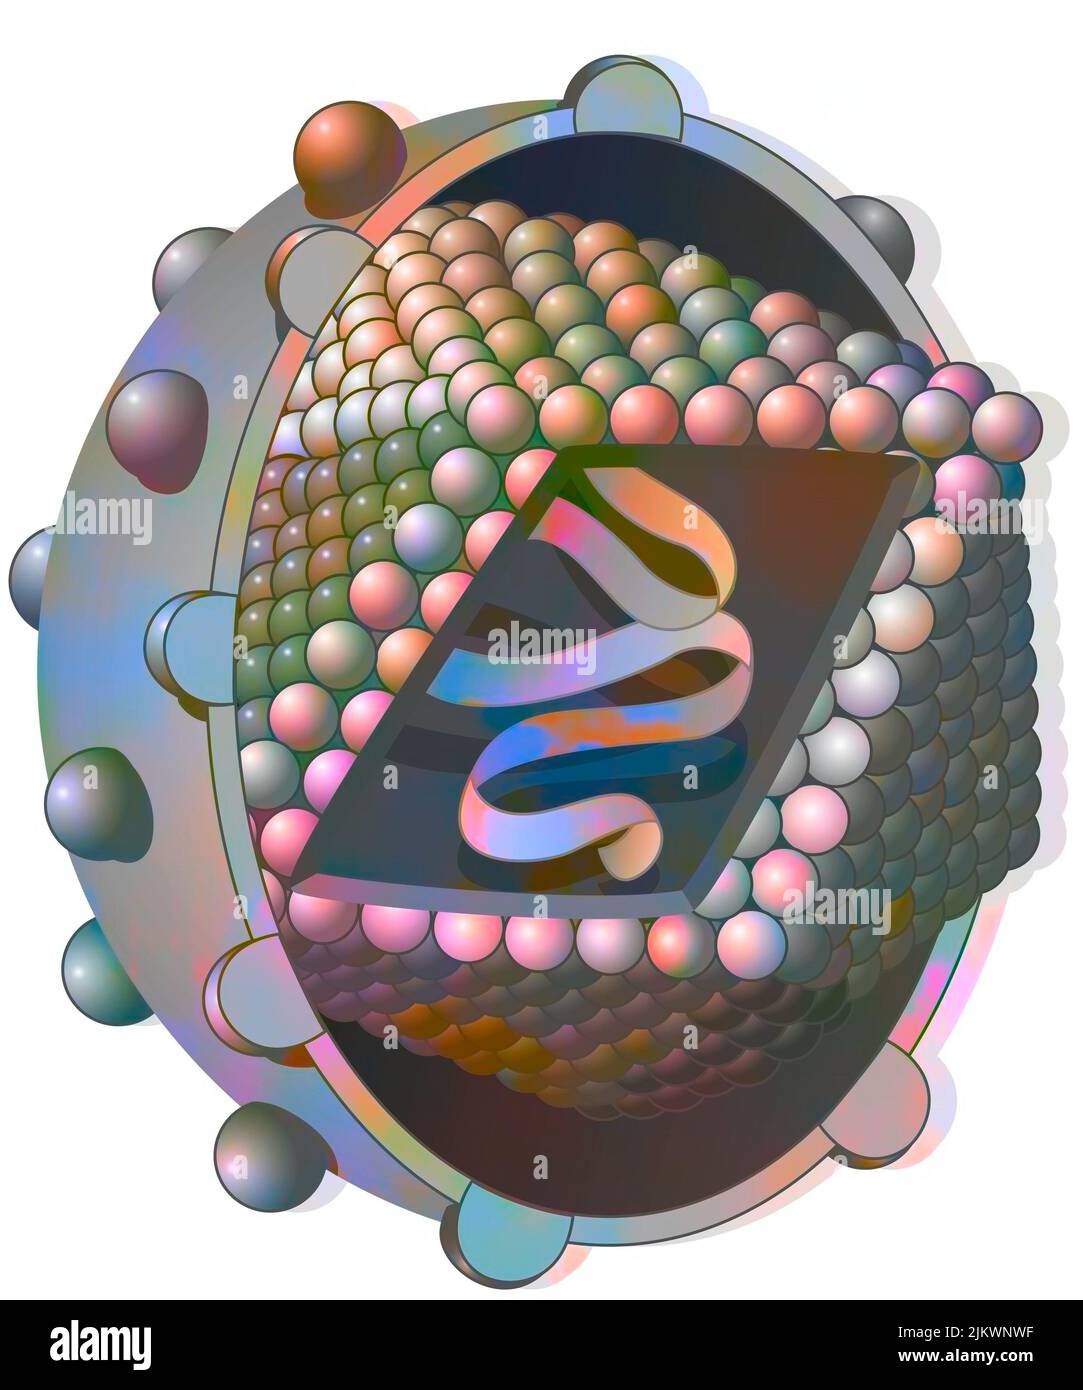

RF2JKWTKH–Canal ionique dépendant du ligand : l'attachement d'une molécule particulière provoque l'ouverture du canal.

RF2JKWPGK–Acide aminé non synthétisé par la voie du ribosome dont seul l'acide de gauche peut être synthétisé par les ribosomes. C'est pourquoi la synthèse des antibiotiques est si complexe.